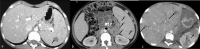

The purpose is to discuss abdominal tuberculosis mimicking malignancy involving the abdominal viscera. TB of the abdominal viscera is common, especially in countries where tuberculosis is endemic and in pockets of non-endemic countries. Diagnosis is challenging as clinical presentations are often non-specific. Tissue sampling may be necessary for definitive diagnosis. Awareness of the early and late disease imaging appearances of abdominal tuberculosis involving the viscera that can mimic malignancy can aid detecting TB, providing a differential diagnosis, assessing extent of spread, guiding biopsy, and evaluating response.